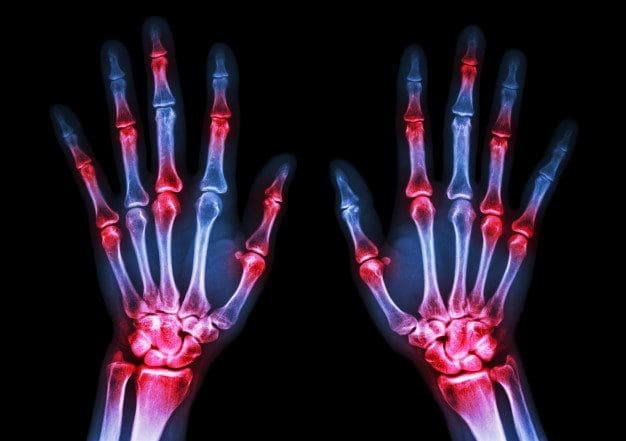

Patients with RA typically present with pain and stiffness in multiple joints. The wrists, proximal interphalangeal joints, and metacarpophalangeal joints are most commonly involved. Morning stiffness lasting more than one hour suggests an inflammatory etiology. Boggy swelling due to synovitis may be visible (Figure 1), or subtle synovial thickening may be palpable on joint examination. Patients may also present with more indolent arthralgias before the onset of clinically apparent joint swelling. Systemic symptoms of fatigue, weight loss, and low-grade fever may occur with

Baseline complete blood count with differential and assessment of renal and hepatic function are helpful because the results may influence treatment options (e.g., a patient with renal insufficiency or significant thrombocytopenia likely would not be prescribed a nonsteroidal anti-inflammatory drug [NSAID]). Mild anemia of chronic disease occurs in 33 to 60 percent of all patients with RA,20 although gastrointestinal blood loss should also be considered in patients taking corticosteroids or NSAIDs. Methotrexate is contraindicated in patients with hepatic disease, such as hepatitis C, and in patients with significant renal impairment.21 Biologic therapy, such as a TNF inhibitor, requires a negative tuberculin test or treatment for latent tuberculosis. Hepatitis B reactivation can also occur with TNF inhibitor use.22 Radiography of hands and feet should be performed to evaluate for characteristic periarticular erosive changes, which may be indicative of a more aggressive RA subtype.10

Rheumatoid arthritis, or RA, is the most common type of arthritis. RA is an autoimmune disease, caused when the immune system, the human body’s defense system, attacks its own cells and tissues, particularly the joints. Rheumatoid arthritis is frequently identified by symptoms of pain and inflammation, often affecting the small joints of the hands, wrists

In conclusion, rheumatoid arthritis is a chronic, autoimmune disease which causes painful symptoms, such as pain and discomfort, inflammation and swelling of the joints, among others. The joint damage characterized as RA is symmetrical, meaning it generally affects both sides of the body. Early diagnosis is essential for